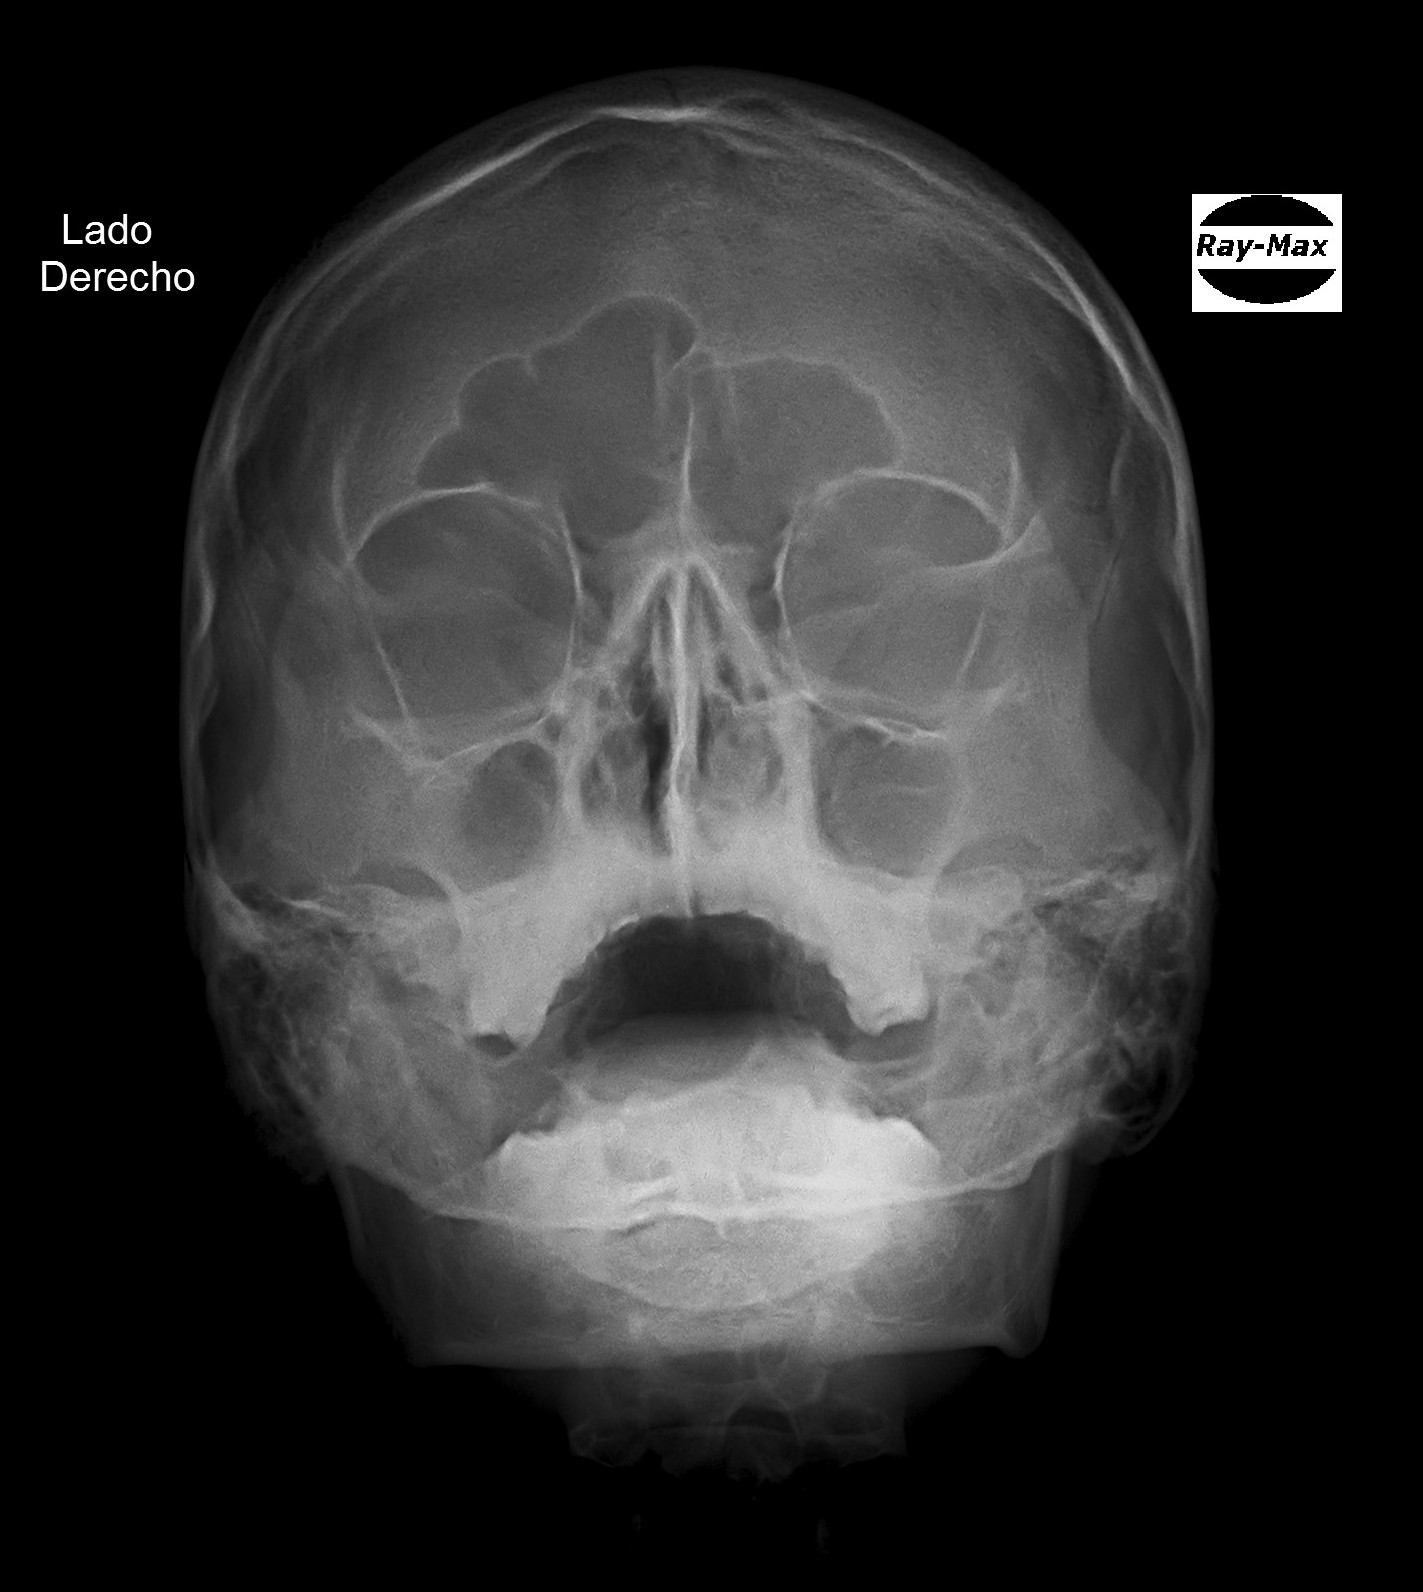

Debido a que trabajamos con la más avanzada tecnologia todas las radiografias digitales pueden ser entregadas/enviadas: Impresas en peliculas radiográficas con formato médico de alto contraste, CD y/o correo electrónico.